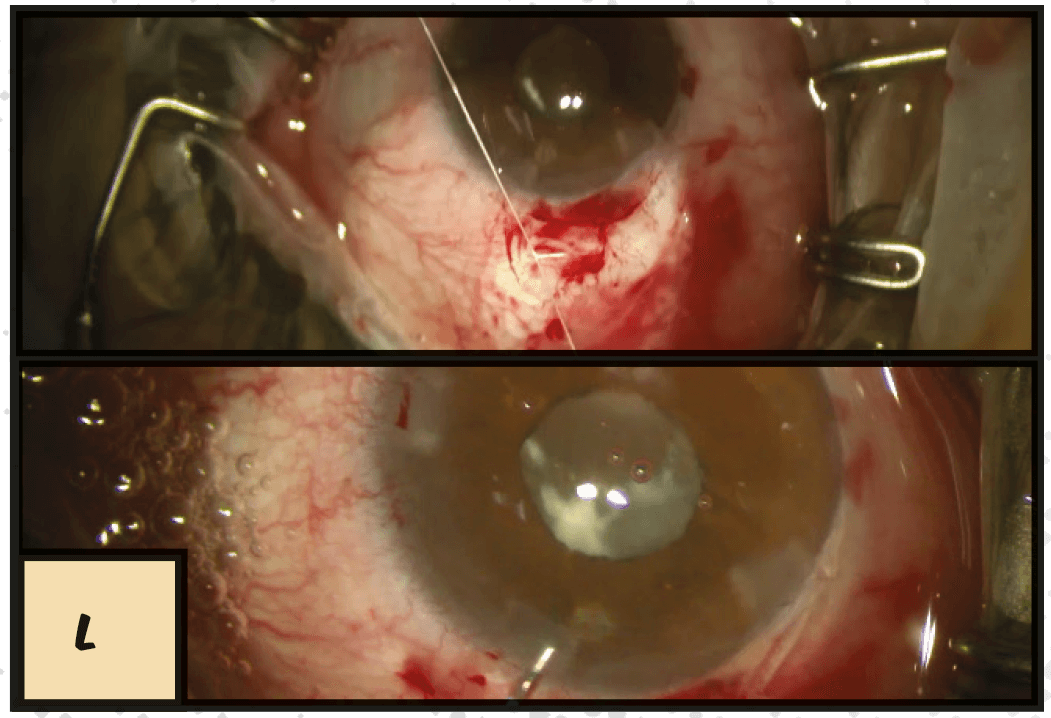

L. Here we refixated the haptics with that suture again. We’ve got a well-centered IOL here, and a well-positioned small incision technique. So we’re ending with a good score!